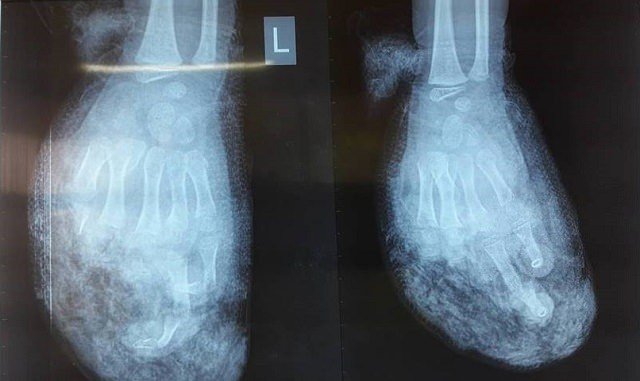

Bé trai 7 tuổi chơi chiếc điện thoại trong lúc đang được cắm dây sạc pin, bất ngờ điện thoại phát nổ.